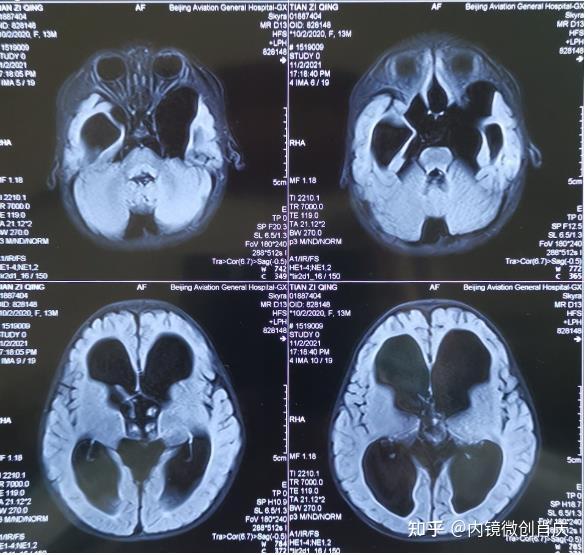

【临床病例分析】鞍区rathke囊肿的诊断及治疗方案

图片尺寸496x527

泰安市中心医院卒中中心成功为两例鞍区病变(rathke囊肿)患者实施眉弓